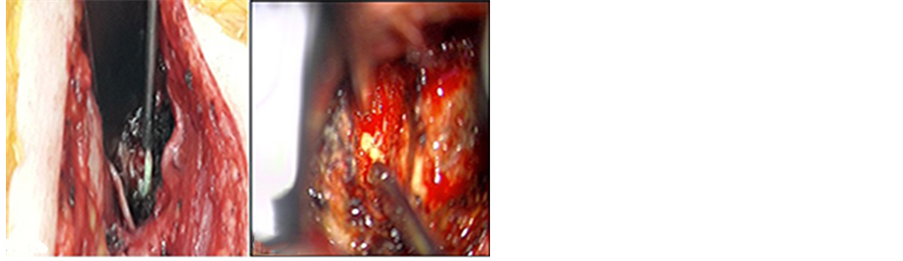

The patient underwent a second surgical procedure. A high right neck horizontal incision just below the level of the mandible was used, extending from the level of the sternocleidomastoid to the midline. After cutting the platysma, the deep neck structures were dissected. The major vessels were identified, and were retracted laterally. The larynx, trachea and underlying esophagus/hypopharynx were retracted medially, revealing the retropharyngeal space and longus colli muscle. A wide exposure was done without the need for submandibular resection [13] . The posterior aspect of the hypopharynx was carefully inspected and a small circular defect was identified representing the fistulous tract of a 1.5 cm diameter adherent to the abscess at C2-C3 disc level verified using C-arm. After minimal manipulation at the C2-C3 disc space, pus was expressed from the infected disc (Figure 3(a), Figure 3(b)).

Figure 3. (a) (left) Intraoperative suctioning of purulent discharges (Macroscopic view); (b) (right) Intraoperative suctioning of purulent discharges (Microscopic view).